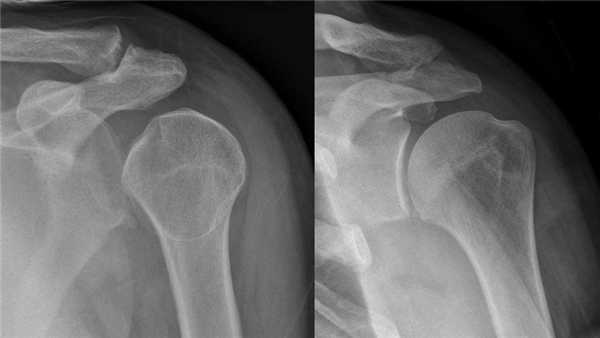

Диагностика вывиха включает себя детальный осмотр пациента, ощупывание поврежденного сустава и назначение рентгенографии в двух проекциях поврежденного сустава. С помощью полученного рентгена врач выявляет тип вывиха, нет ли перелома, и определяется со способом вправления. В более серьезных случаях для уточнения диагноза врач может назначить компьютерную и магнитно-резонансную томографию. При наличии серьезных повреждений необходима консультация хирурга.